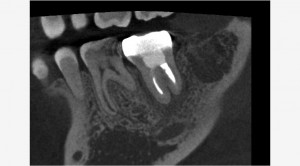

ふつうはここで安心してしまうのですが、私的に、あれだけ盛った人工骨は本当に骨になったのか気になったので、患者さんにお願いしてCTを撮影させていただきました。

うん!素晴らしい!!

このスライス!!素晴らしい。

うまくいって良かった(^^♪